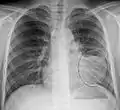

Normal lateral CXR

Right lower lobe pneumonia as seen on a lateral CXR